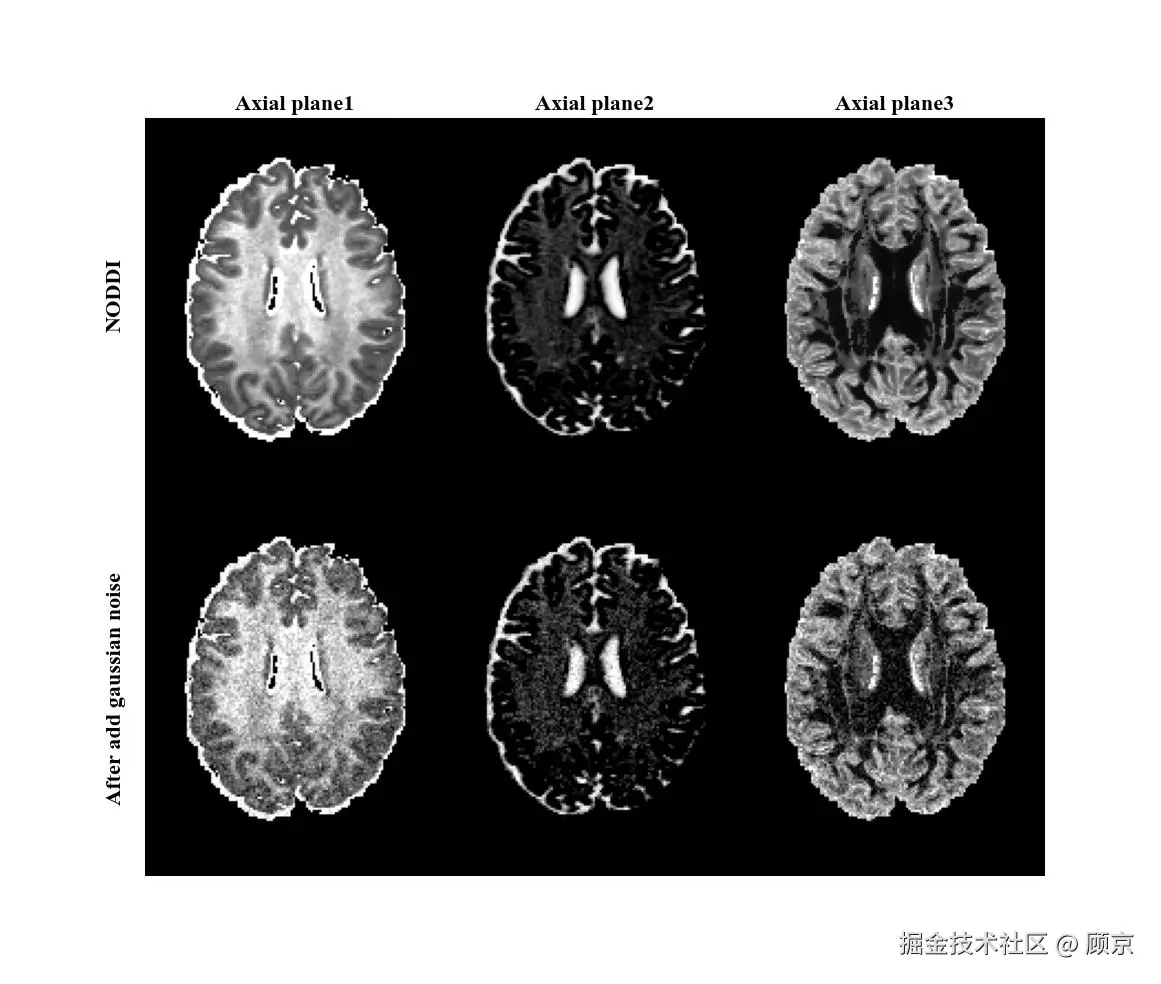

其中,xxyy是像素相对于核中心的偏移,σ\sigma是标准差,可以决定模糊程度。通过这个高斯核对图像进行卷积,就可以实现高斯模糊,如图6所示。

图6 高斯模糊操作